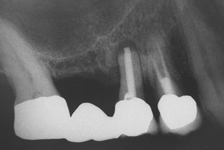

Jedná se o vyzvednutí membrány, která čelistní dutinu vystýlá, pod vyzvednutou membránou vznikne kapsa, kam se umístí augmentační materiál, do kterého se zavedou implantáty.

Vhojení implantátů se při této operaci prodlužuje na 6-12 měsíců.

- Uzavřený, interní, vnitřní, crestální sinus lift

- Otevřený, externí, vnější, laterální sinus lift